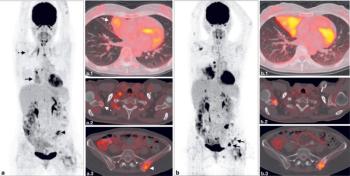

Metformin appeared to increase glucose uptake in lung cancer cells, according to results from a phase II trial.

Researchers examined how metformin and TKI therapy did in combatting lung cancer.